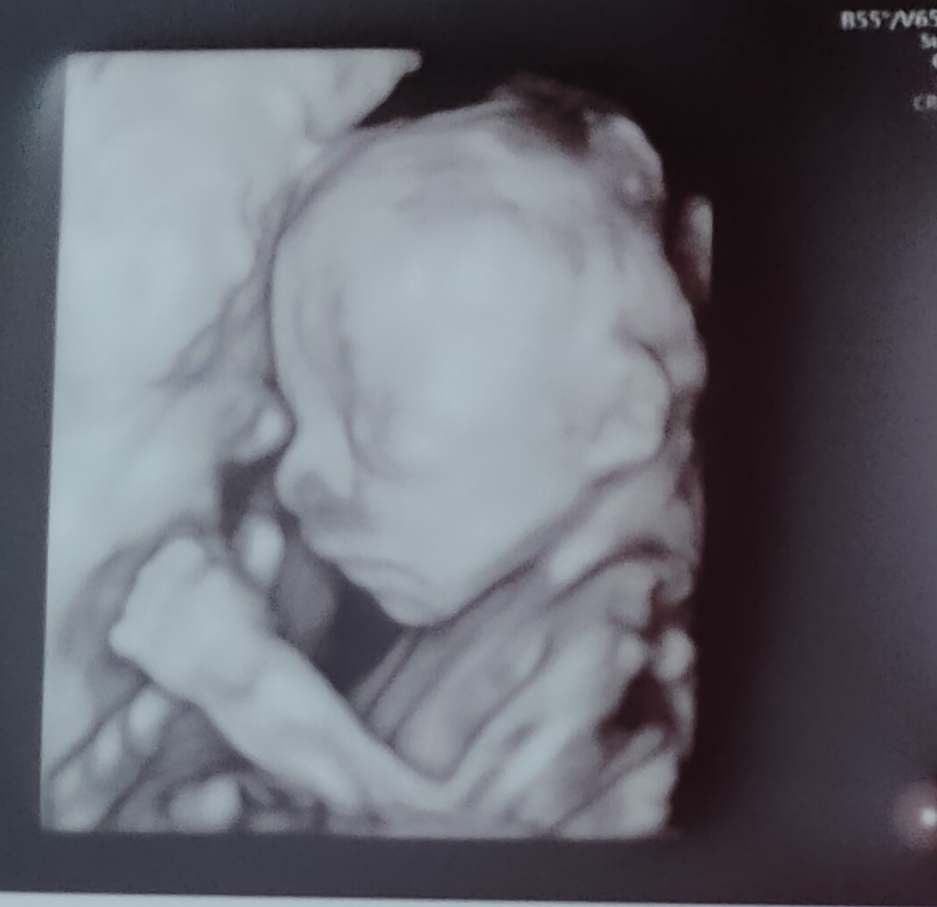

Ahooj, tak se po delší odmlce ozývám 😁 Nejak nebyl čas ani nálada,ja nevím ty hormony to je katastrofa 🥺 jsem buď vzteklá jak pes nebo se mi chce brečet, všechno a všichni mi vadí 🤣 Nemůžu jíst žádné maso,ryby ani šunky,max občas zakamuflovane kuřecí, takže jídlo je jedno velké peklo🤣 Minulý tyden jsme měli 2.screening, naštěstí je vse ok☺️ Dozvěděli jsme se i pohlaví,ale tak, že nám ho doktor napsal na papirek a s papirkem jsme jeli pro balonek, který naplní barevnýma konfetama, ten jsme pak doma praskli a natočili to na video abychom to pak poslali ostatním 😁 schválně, má někdo tip?

Tak já si tedy podle te fotky myslím, že to bude kluk 🥳💙

@kikika87 faakt kez by🤣 spis mi to prijde cim dal horsi🤣 co u tebe?😁 Zatim mam nahore 5 kilo,snad jen v brichu a prsou,ale to teprv na prijde. Strasne jsem si přála holčičku, asi ani nejak nepocitala s klukem a samozrejme modro 🤣

@kikika87 jmeno pro kluka uz máme tak dva roky🤣 Bude to Tobiáš ☺️ zas kdyby to byla holka tak nemusíš tolik řešit vybavicku a mala by mela kamosku😁 uz by se pomalu mohlo ukazat vid? Mas malinko nahore,ja jsem 22+4 a jsem proti tobe jak slon🤣 s tím ze mam 157cm je to des🤣 Neco malinko už máme,ale na oblecky jsem náročná, tím ze to nemůže byt ta moje vysnena ruzova tak shanim takovou tu krásnou blede modrou a bilou a v obchodech je sama hneda seda apod😳 co ty uz neco mas?